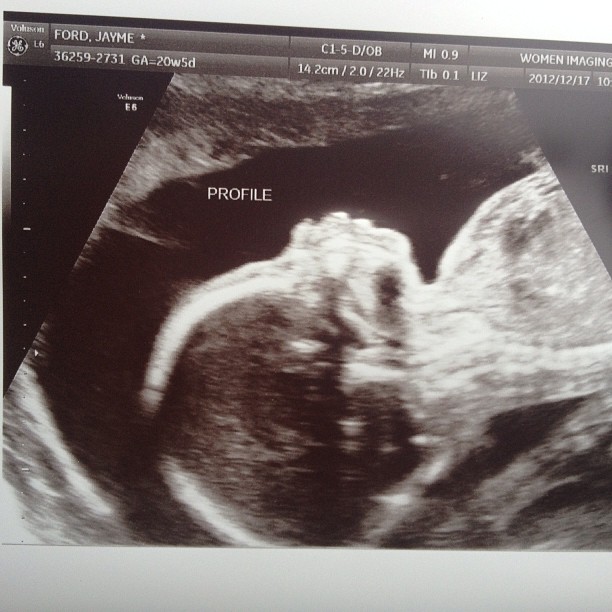

So this week is going to take on a bit more serious of a tone....its a bit of a long one but there are photos, I promise :) On Dec 17th we had our 20 week ultrasound and was informed that I had a 2 v...